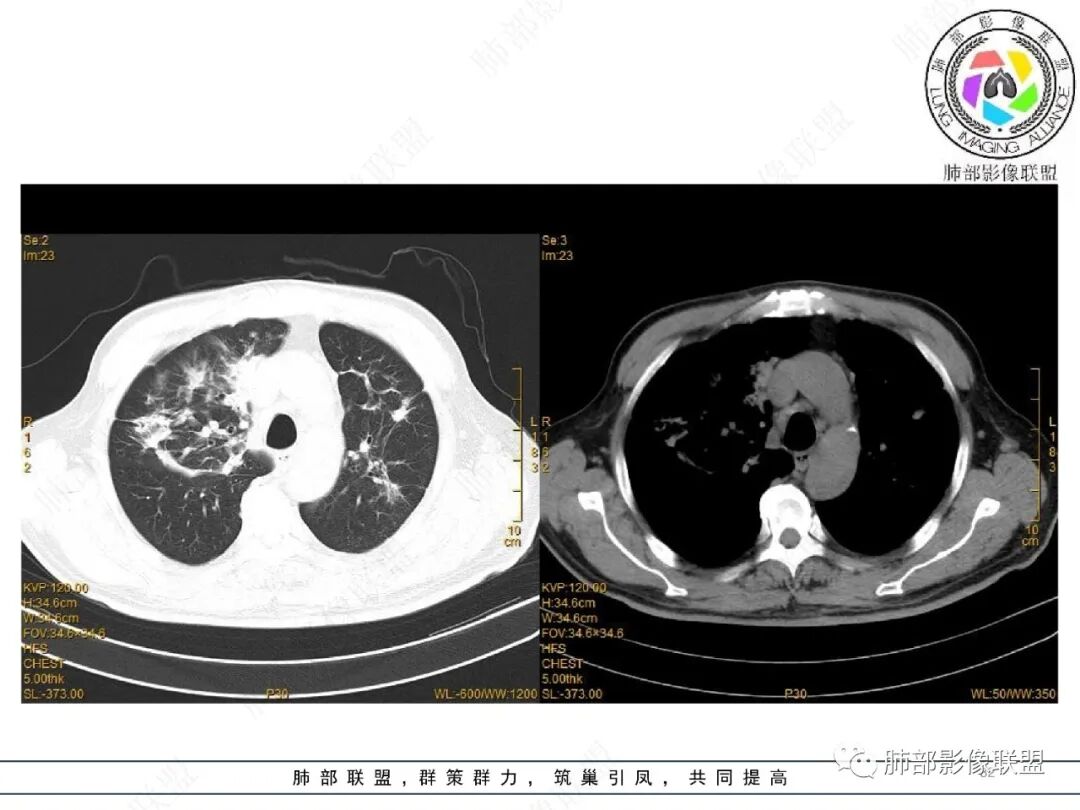

2022.2.17CT显示两肺中内带多发结节影、斑片影、条索影,部分病灶侧向融合与胸膜平行。部分病灶沿着支气管血管束分布、其内支气管稍扩张。部分病灶呈反晕征。大部分病灶边界显示清晰,部分病灶周围可见边界不清的GGO。2022.4.12CT显示两肺中内带多发结节影、条索状、条带状高密度影,边界收缩平直凹陷,大部分病灶沿着支气管血管束分布,亦有位于胸膜下侧向融合与胸膜平行的病灶。总体与第一次CT对比两肺病灶明显吸收。

3、病例小结:

老年男性,两肺多发病灶,整体呈OP样改变,至于是原发性还是继发性的OP,需要临床鉴别。此病例穿刺结果是隐球菌。该病例CT上缺乏隐球菌典型的“在那遥远的胸膜下,多个蘑菇兄弟,可以侧向融合呈长串状与胸膜平行”影像表现,更多是OP样改变,仅凭临床表现或影像资料诊断隐球菌难度比较大。当然也不除外二元论,导致隐球菌的影像表现被掩盖。